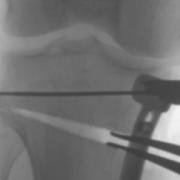

Laminar spreaders open the wedge of a high tibial osteotomy.